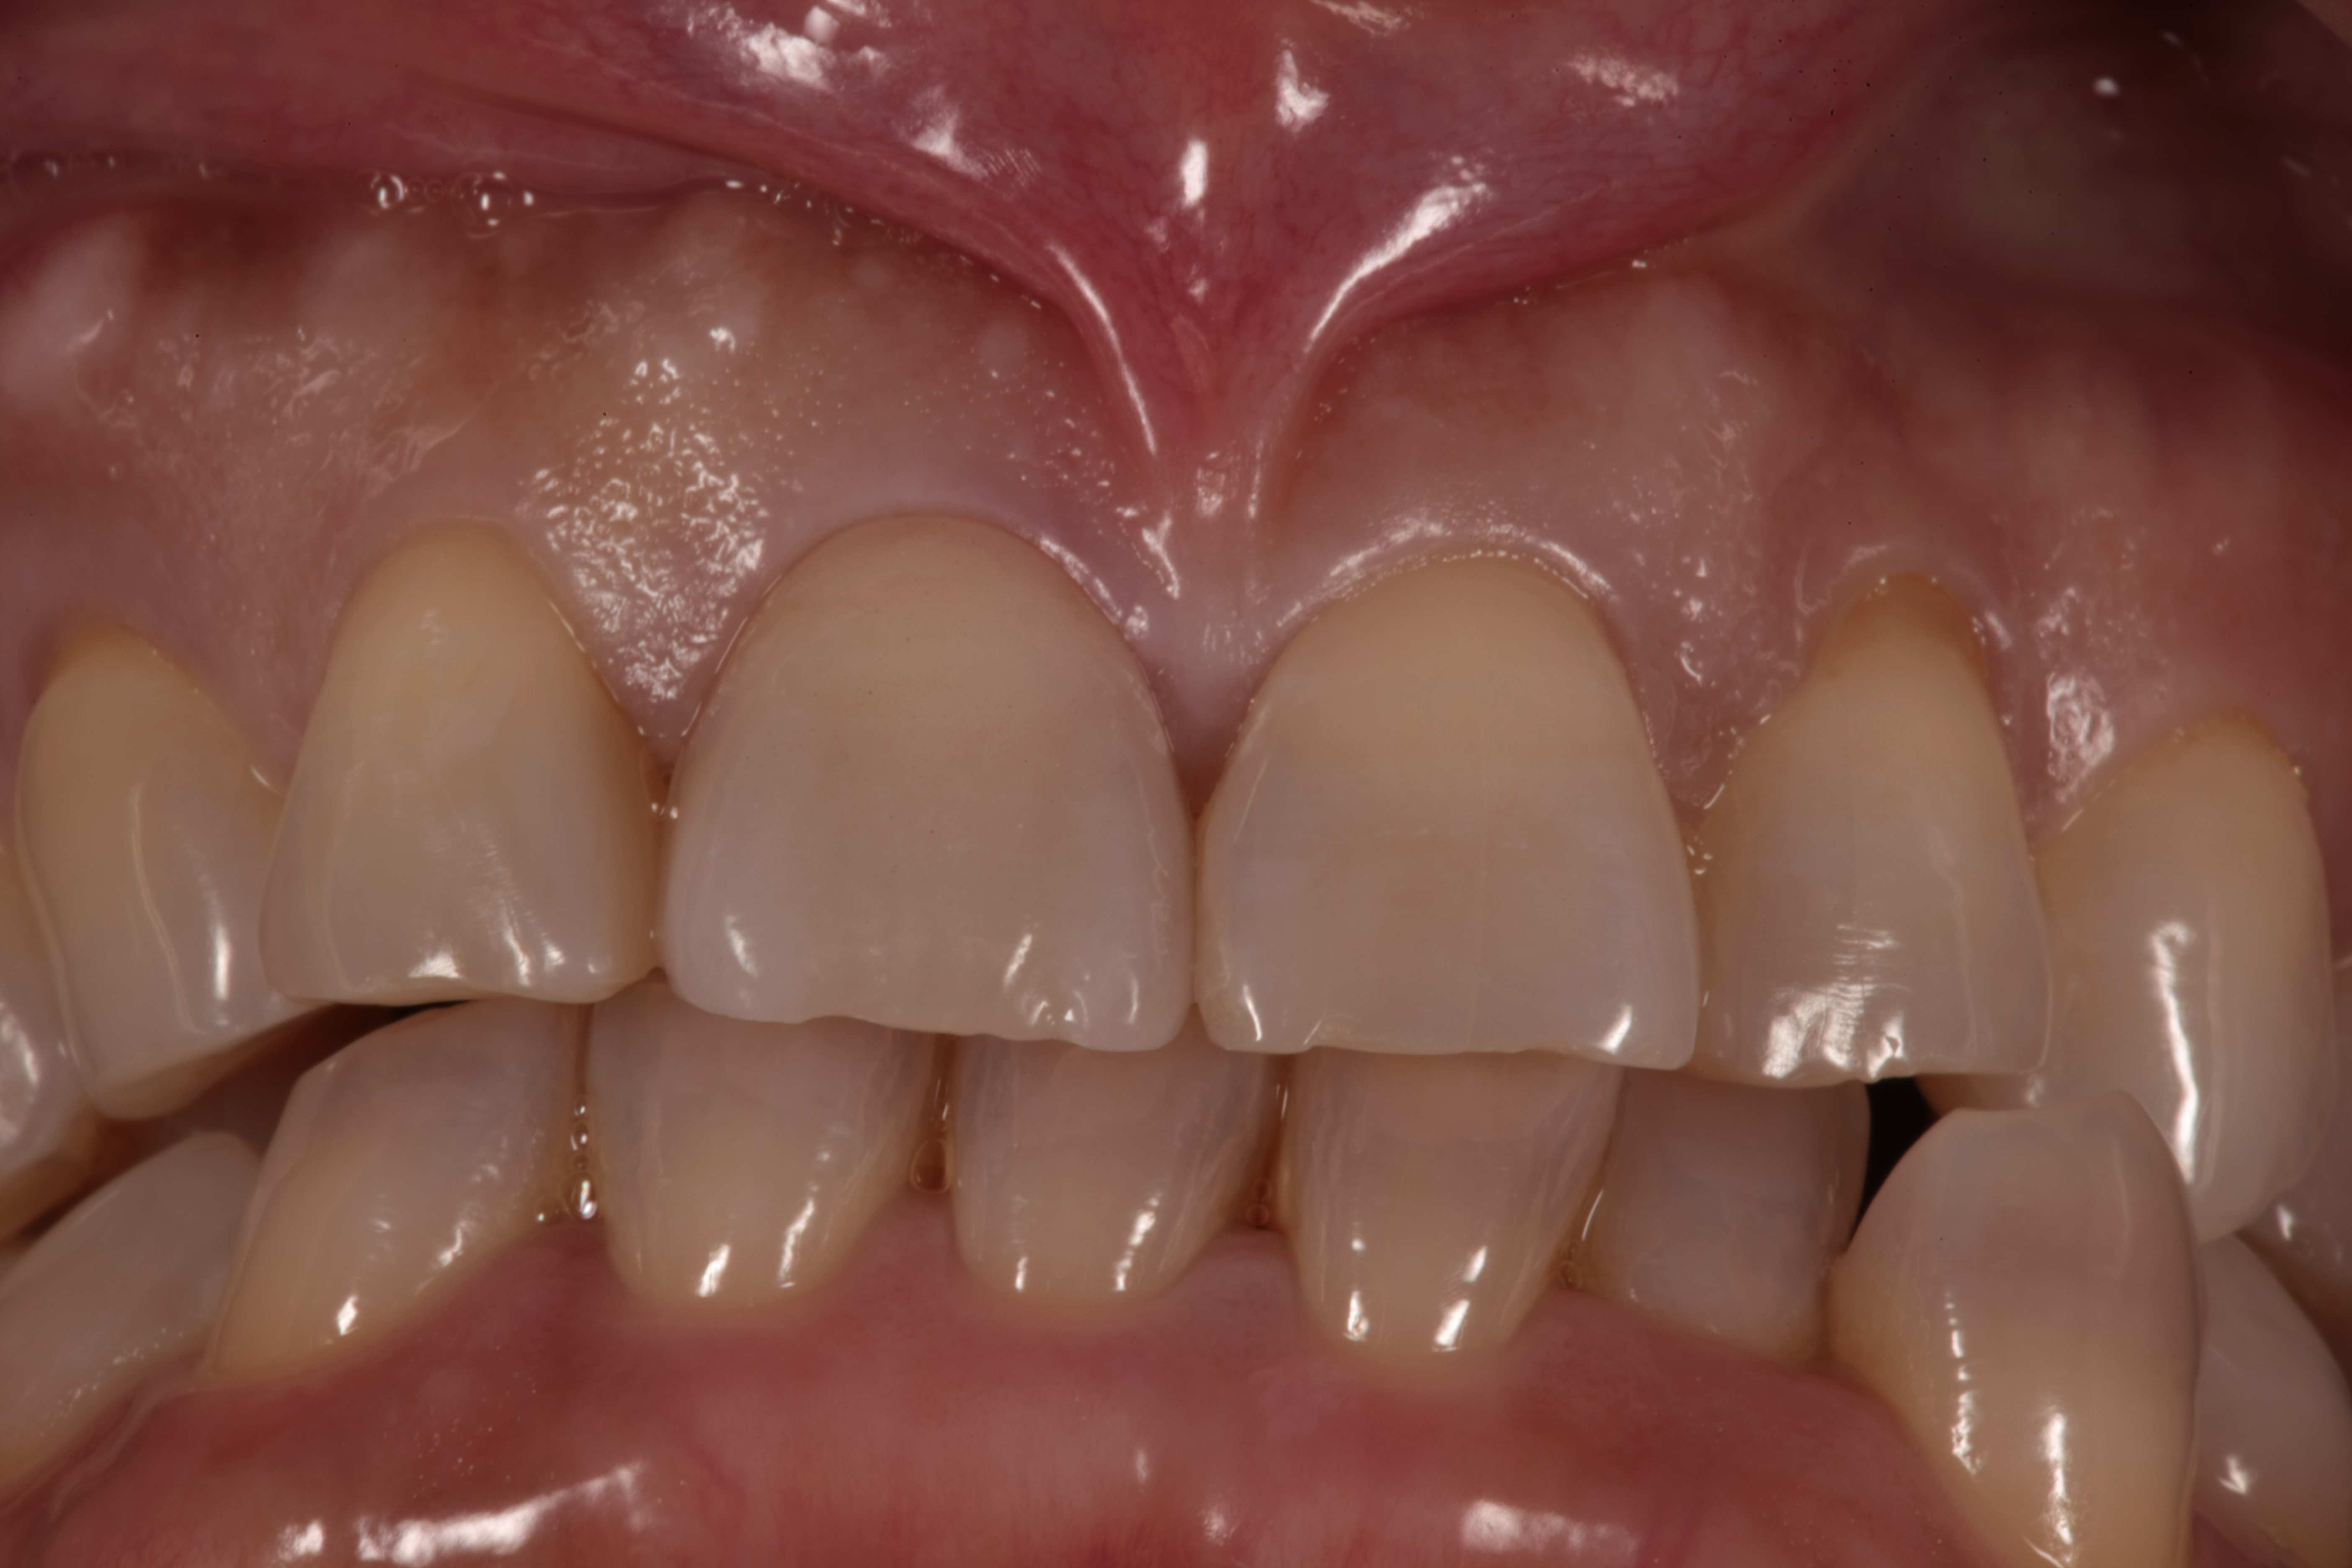

最終的な歯が仕上がった状態です(*^-^*)

どこを治療したか分からない仕上がりですね!

綺麗にセラミックの歯が入っています。

写真を撮った時の前歯の目立ちがなくなり綺麗に写ります。

前歯にコンプレックスがある方は、笑った時の写真の口元が気になります。

歯が目立ち、笑わないようにしたり隠したりと気にしながら生活している方が多いです。

コンプレックスがなくなると生活の質が上がります(^^)/